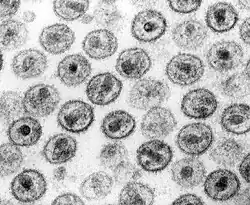

En 1983, Robert Gallo n'est pas parvenu à isoler le virus dans les échantillons sanguins de patients atteints du sida. Willy Rozenbaum pense alors que chez les malades du sida, la plupart des cellules infectées sont détruites et que c'est la raison du manque de résultats dans ces tentatives d'isolement du virus. Il a alors l'idée de chercher le virus dans un organe riche en lymphocytes, les ganglions lymphatiques de personnes malades mais qui ne sont pas encore en phase de sida. En janvier 1983, Willy Rozenbaum prélève un échantillon d'un patient atteint d'une lymphadénopathie, pathologie identifiée comme une maladie opportuniste du stade pré-sida. L'échantillon est mis en culture et Françoise Barré-Sinoussi découvre une activité de transcriptase inverse, confirmant la présence d'un rétrovirus. Une apoptose apparaît et l'adjonction de globules blancs à la mise en culture relance alors l'activité de transcriptase inverse. Un examen au microscope électronique a permis de visualiser, pour la première fois, le virus[8], le 4 février 1983.

Le VIH-1 est un virus sphérique d'un diamètre moyen de 145 nanomètres[42]. Comme de nombreux virus infectant les animaux, il dispose d'une enveloppe composée d'un fragment de la membrane de la cellule infectée. Dans cette enveloppe lipidique sont insérés des trimères de glycoprotéine d’enveloppe (Env). Chaque protéine Env est formée de 2 sous-unités : une sous-unité de surface gp120 et une sous-unité transmembranaire gp41. La surface d’un virus VIH contiendrait en moyenne seulement 14 trimères Env[43]. Lors de l'attachement du virus à la cellule, la protéine Env gp120 se lie à un récepteur CD4 présent à la surface des cellules CD4+ du système immunitaire. C'est pour cette raison que le VIH n'infecte que des cellules ayant ce récepteur à leur surface, qui sont en très grande majorité les lymphocytes CD4+.